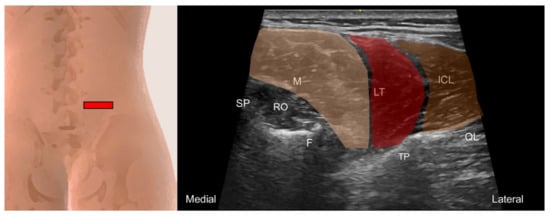

6.3. Quadratus Lumborum and Psoas Major

6.3.1. Anatomy

6.3.2. Sonographic Scanning

6.3.3. Clinical Relevance